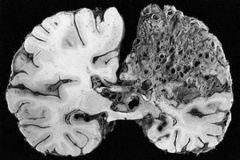

非典型脑膜瘤who二级严重吗?能治好吗? 脑膜瘤 是脑膜的肿瘤,...

左顶镰旁 脑膜瘤 是癌症吗?手术未做干净怎么办?由于大脑镰旁...